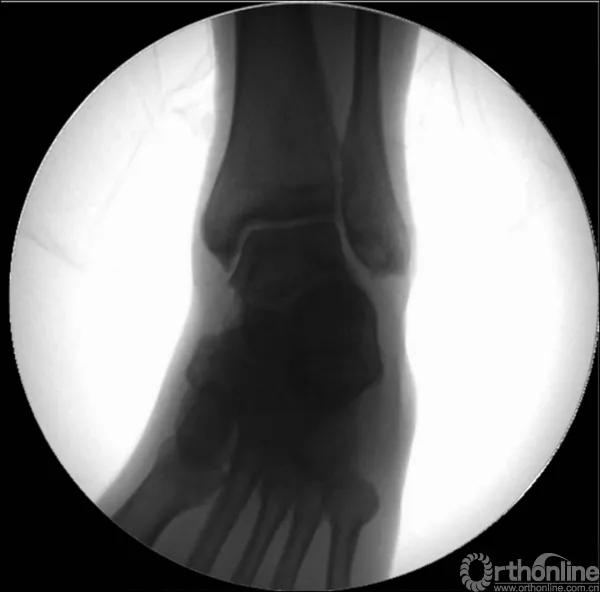

X线诊断:标准的踝关节影像学评估应包括3个位相:前后位(图5),踝穴位(内旋15°)(图6),侧位(图7)。

图6 踝穴位(内旋15°)

图7 侧位

当踝关节严重损伤时内外踝及距骨将发生不同程度的移位(图8)。有时外踝骨折会伴有三角韧带的损伤,静态的X线摄片并不能准确地折射踝关节的稳定性,应力位片及MRI检查可完善对踝关节稳定性及韧带损伤的评估(图9)。此时应通过患肢损伤机制及放射资料准确判断踝关节损伤的类型以正确指导复位和固定。有时单纯内踝骨折可能是更为复杂的“Maisonneuve骨折”的一部分,该骨折还包括腓骨近端骨折及韧带联合损伤,故X线检查应投照整个胫腓骨。